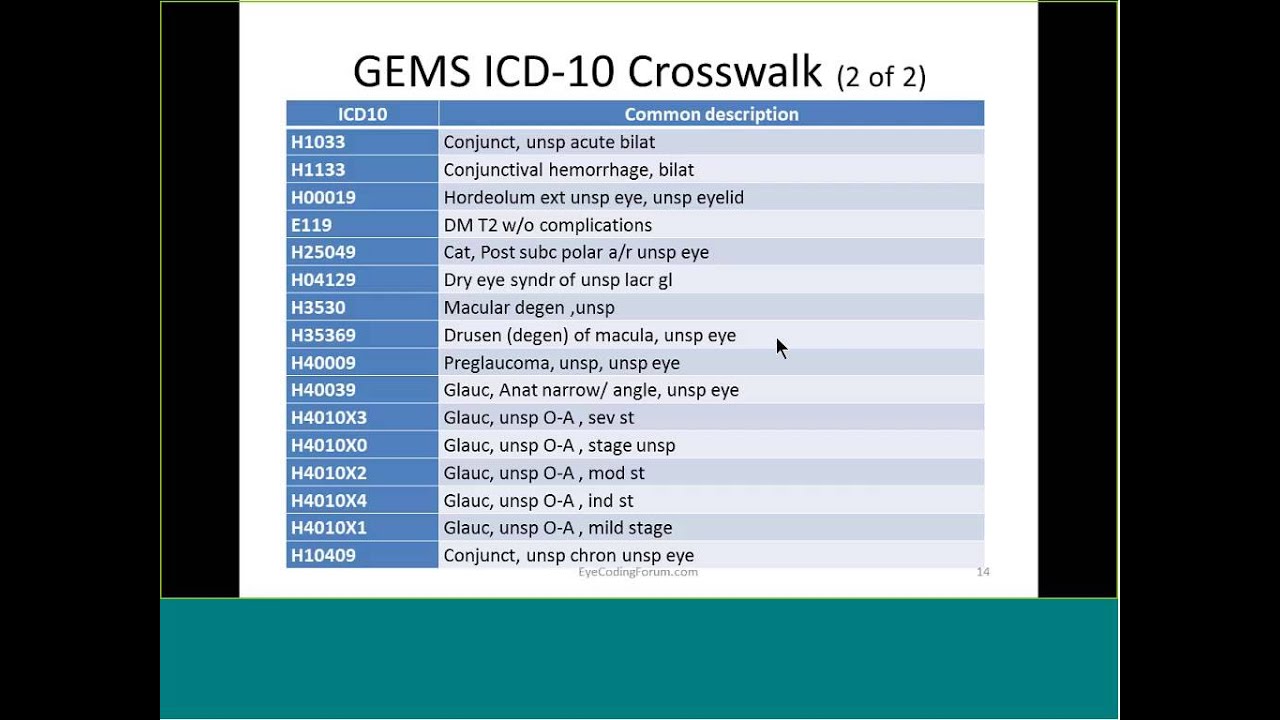

What is the GEM crosswalk?

The General Equivalency Mapping (GEM) crosswalk indicates an approximate mapping between the ICD-10 code P25.8 its ICD-9 equivalent. The approximate mapping means there is not an exact match between the ICD-10 code and the ICD-9 code and the mapped code is not a precise representation of the original code.

What is the GEM crosswalk?

The General Equivalency Mapping (GEM) crosswalk indicates an approximate mapping between the ICD-10 code J43.9 its ICD-9 equivalent. The approximate mapping means there is not an exact match between the ICD-10 code and the ICD-9 code and the mapped code is not a precise representation of the original code.